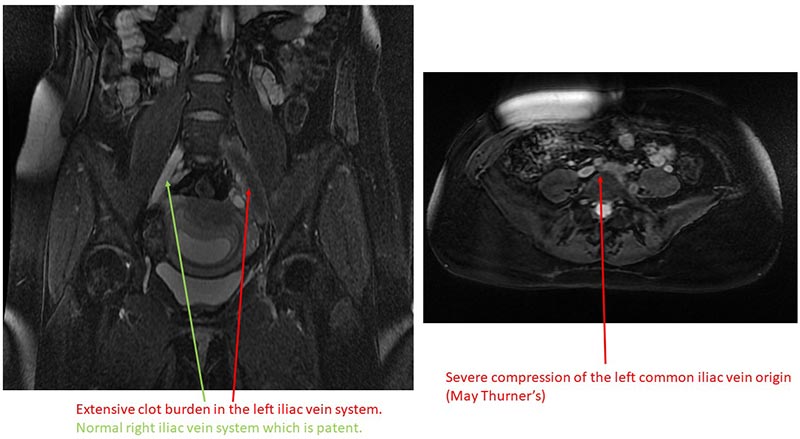

Extensive clot burden in the left iliac vein system and severe compression of the left common vein origin

Extensive clot burden in the left iliac vein system and severe compression of the left common vein origin.

Pregnancy increases the risk for a blood clot five-fold. When we performed the imaging, we discovered that she had May-Thurner Syndrome. Her right iliac artery was compressing the left iliac vein. Several patients with May-Thurner Syndrome typically experience no symptoms and remain undiagnosed, yet some develop DVT like our patient did.

Right iliac artery compressing the left iliac vein